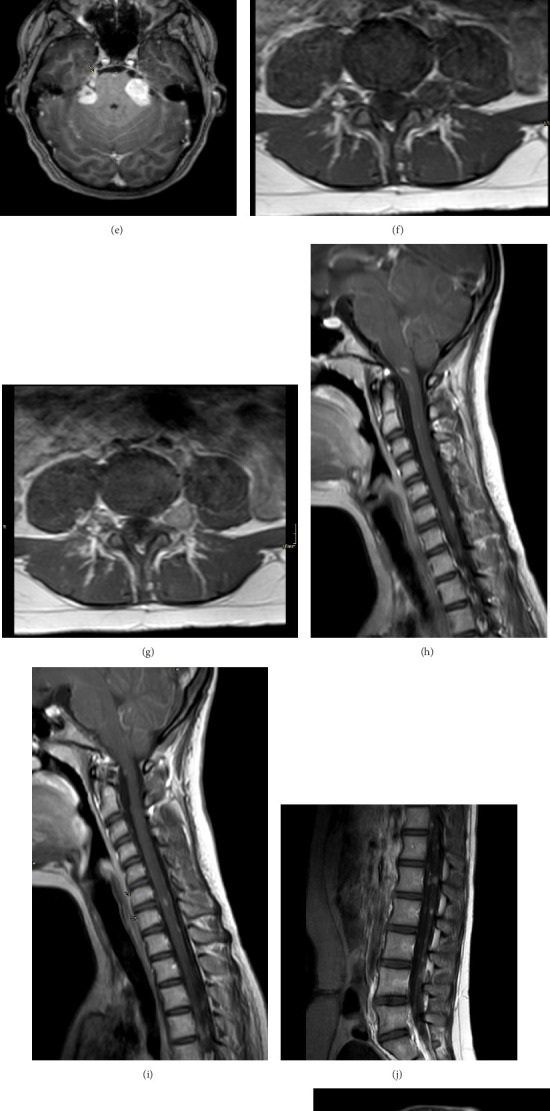

2型神经纤维瘤病(NF2),也称为NF2相关神经鞘瘤病(SWN),是一种罕见的显性遗传性遗传病,主要特征为前庭神经鞘瘤(VSs)以及一系列影响中枢和周围神经系统的其他肿瘤。这些肿瘤包括颅、脊髓、周围神经和皮内神经鞘瘤,颅和脊髓脑膜瘤,以及固有中枢神经系统(CNS)肿瘤,通常是脊髓室管膜瘤。青少年白内障在NF2患者中也很常见,大多数症状为听力丧失和视力障碍。我们提出的情况下,以前健康的12岁女孩谁提出餐后右上腹部疼痛,并被发现有一个大的胆囊积液超声扫描腹部。腹腔镜胆囊切除术后胆囊病理显示胆囊弥漫性受累于良性神经鞘肿瘤,提示神经鞘瘤。进一步的检测证实了NF2的诊断。本病例有助于阐明不寻常的NF2症状,并强调了识别非典型表现以及时干预和管理的重要性。它还增加了诊断和管理NF2的多学科方法的价值。

Neurofibromatosis type 2 (NF2), also known as NF2-related schwannomatosis (SWN), is a rare dominantly inherited genetic disorder mainly characterized by the presence of vestibular schwannomas (VSs) in addition to a range of other tumors that affect both the central and peripheral nervous systems. These tumors include cranial, spinal, peripheral nerve, and intradermal schwannomas, cranial and spinal meningiomas, and intrinsic central nervous system (CNS) tumors, usually spinal ependymomas. Juvenile cataracts are also common in patients with NF2, with most symptoms at presentation being hearing loss and visual disturbances. We present the case of a previously healthy 12-year-old girl who presented with postprandial right upper quadrant pain and was found to have a large hydrops of the gallbladder on ultrasound scan of the abdomen. Pathology of the gallbladder post laparoscopic cholecystectomy showed diffuse involvement of the gallbladder by a benign nerve sheath tumor that was suggestive of schwannoma. Further testing confirmed the diagnosis of NF2. This case helps shed light on unusual NF2 symptoms and underscores the importance of recognizing atypical presentations for timely intervention and management. It also adds value to a multidisciplinary approach in diagnosing and managing NF2.